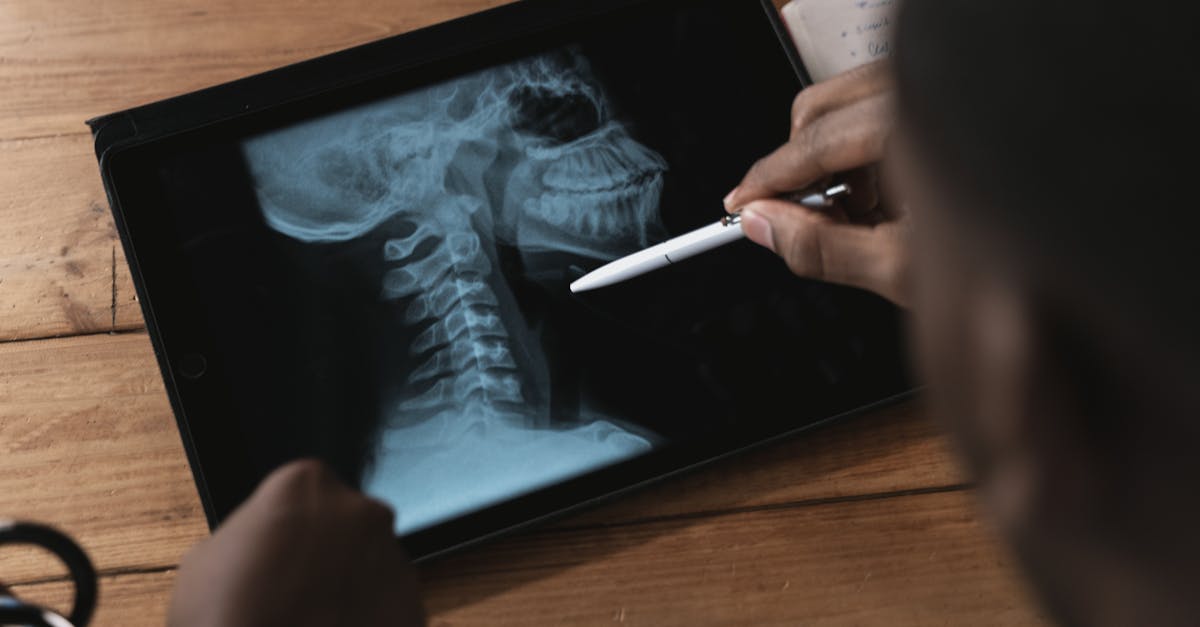

Décompression neurovertébrale : une solution durable pour améliorer la posture cervicale chez les patients souffrant de maux de cou

EN BREF En bref, la décompression neurovertébrale est une solution innovante pour soulager les maux de cou et améliorer la posture cervicale des patients. Accessible dans […]